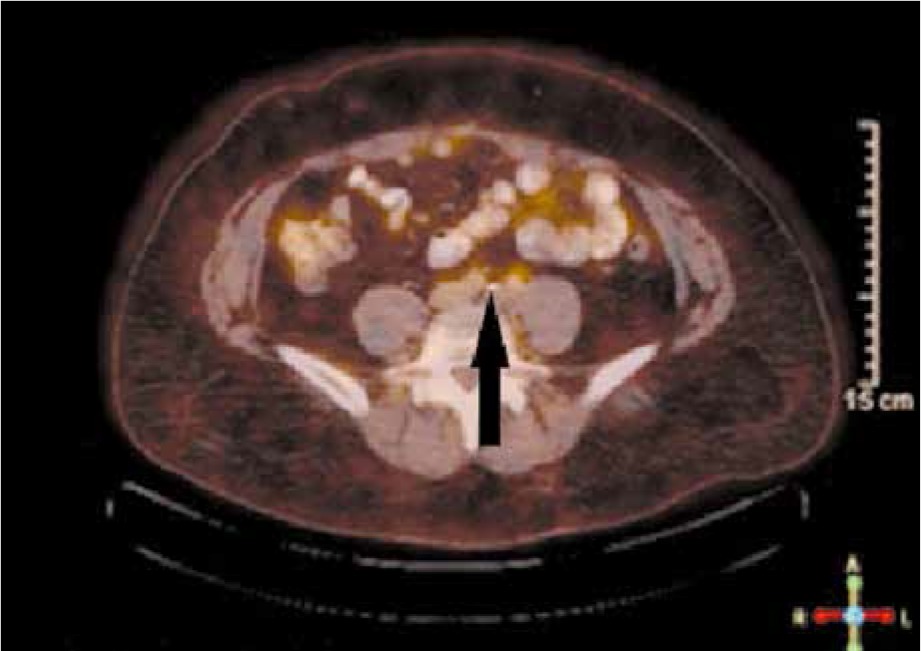

During the first 12 months there were no signs of disease recurrence. Because the patient reported having a ventral hernia at month 15 after surgery, a surgical correction was planned after check-up. A CT of abdomen and pelvis was done with a solitary enlarged LN in the region of the left common iliac artery, measuring 19/13 mm. A confirmatory PET/CT showed no other secondary sites (Fig. 1). The metastatic burden was considered as low and radically resectable. As an oligo-metastatic first progression with only one LN involved, a surgical approach was considered: elective dissection in the region of the common iliac artery to the left followed by correction of the hernia via hernioplasty with a mesh. A conglomerate of 6 common iliac LNs was dissected (Fig. 2), and the final histology report confirmed a metastasis of clear-cell EC in only one of them. Six cycles of pseudo-adjuvant chemotherapy with carboplatin and paclitaxel were done. No serious adverse events were reported, and the patient was again referred to FU. Regular CT of abdomen and pelvis with i.v. contrast enhancement was done every 3 months. Currently, at the end of February 2020 – 36 months after first disease progression – the patient is free of disease with ongoing clinical and imaging complete remission.